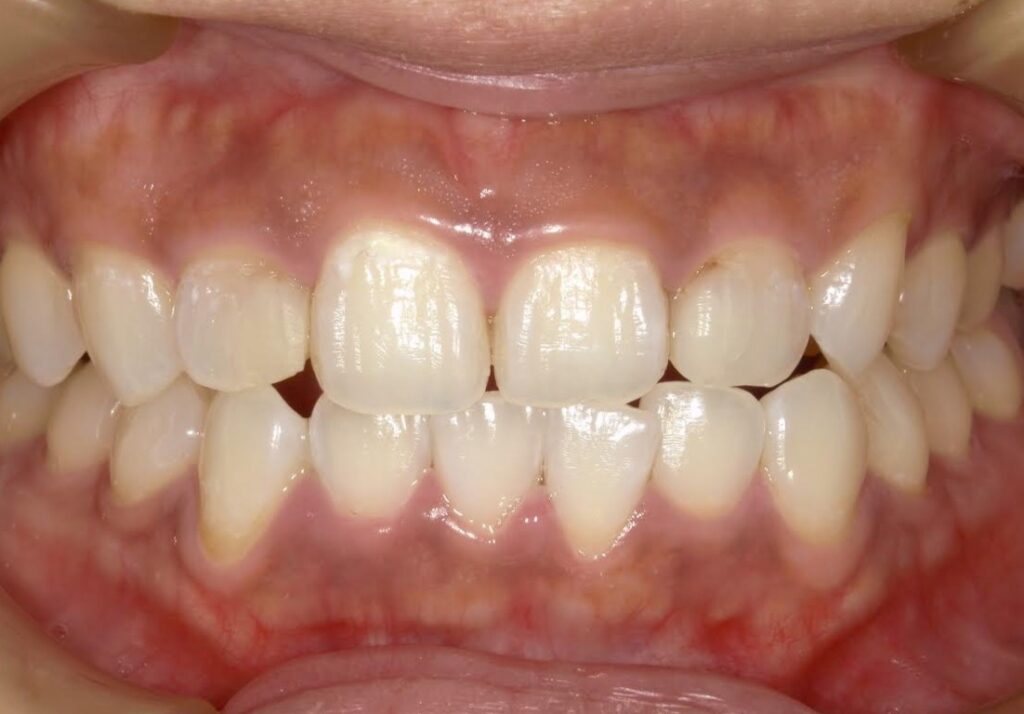

【A様】

Before

After

年齢 | 30代前半 |

性別 | 女性 |

主訴 | 前歯の被せ物の色味が合っていないのでやり直したい |

施術内容 | 色があっていない保険適応のCAD/CAM冠を外して、自費補綴のジルコニアに被せなおしています。 |